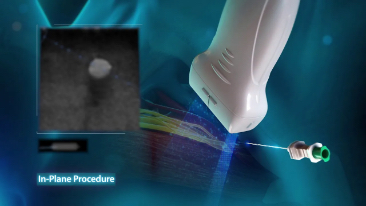

Desde que se fund├│ la compa?├Ła, Mindray ha explorado incansablemente nuevas formas de mejorar la confiabilidad del diagn├│stico. Con la revolucionaria tecnolog├Ła de ZONE Sonography?, la nueva plataforma ZST+ de Resona?7 lleva la calidad de la imagen por ecograf├Ła a un nivel superior mediante el procesamiento de datos de canal y la adquisici├│n de zona.

Adem├Īs de la calidad de imagen de primer nivel, Resona?7 tambi├®n mejora las capacidades de investigaci├│n cl├Łnica con el revolucionario V?Flow para la evaluaci├│n hemodin├Īmica vascular y con la adquisici├│n de planos m├Īs inteligente a partir de conjuntos de datos 3D para el diagn├│stico del SNC fetal. Al combinar el funcionamiento multit├Īctil basado en gestos m├Īs intuitivo y todas las caracter├Łsticas cl├Łnicas esenciales, Resona?7 realmente lidera las novedades en innovaci├│n de ecograf├Łas.